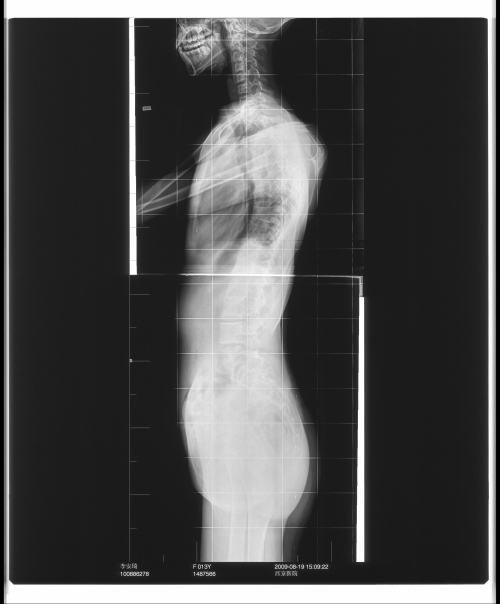

脊柱侧弯术前